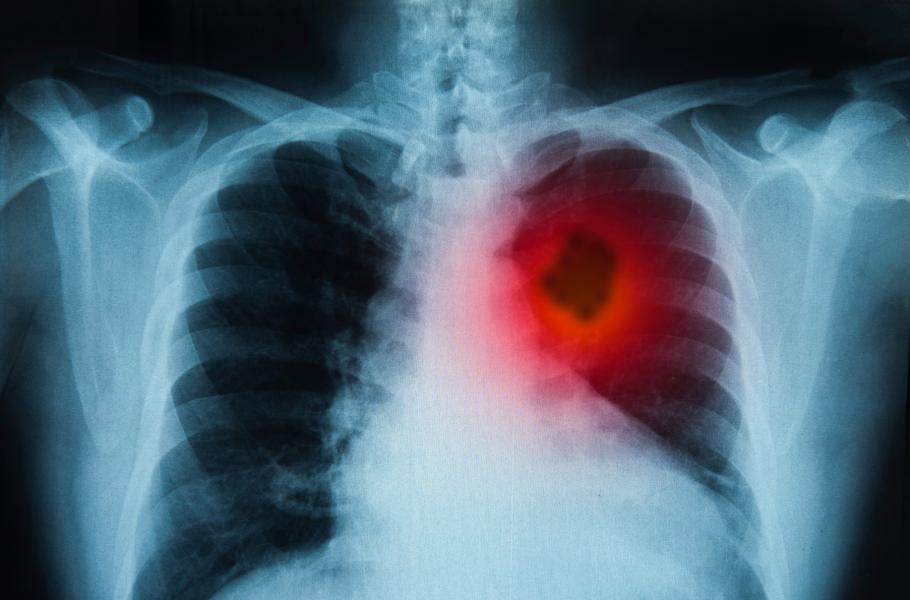

Rakovinu plic je možné léčit podle typu nádoru chirurgicky, chemoterapií či radioterapií .

Vlad prodělal všechny dostupné typy léčby. Podrobil se chemoterapii i ozařování. Jeho nádory však měly tuhý kořínek a vzdorovaly všemu. Lékaři přiznali, že vyčerpali poslední možnosti. Pro Vlada už mohou udělat jediné – zajistit mu důstojné umírání s co nejmenším utrpením.

Pro Joa, Elen a Vlada představovala poslední šanci vakcína tvořená bílkovinou produkovanou nádorovými buňkami. Pokud by se podařilo podat Vladovi bílkovinu tak, aby její přítomnost zaznamenal jeho imunitní systém, mohlo by se pacientovo tělo začít proti zhoubnému nádoru bránit. Zničilo by některé nádorové buňky a jejich obsah by se vylil. Tím se buňkám imunitního systému zpřístupní další molekuly typické pro Vladův nádor a bílé krvinky na rakovinu zaútočí v druhém sledu.